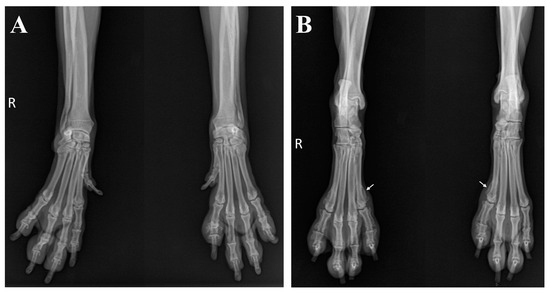

2. Case Description

3. Diagnostic Assessment, Intervention, and Outcomes